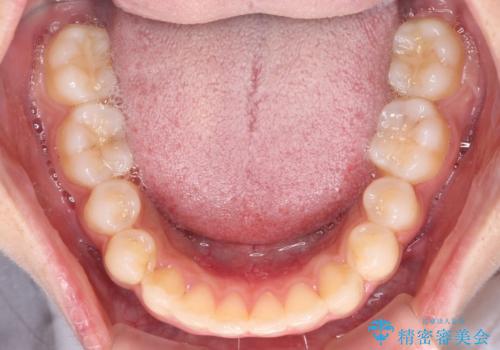

- 上下前歯のデコボコを気にして来院された患者様です。

前歯のセラミックが装着されている歯は、歯根が短くなっており、他院では抜けてしまうので矯正はできないと言われていたようです。

患者様と相談し、抜けてしまった場合にはインプラントあるいはブリッジによる補綴治療が必要となることを確認し、極力歯根に負担のかからないような仕上がりで治療を進めて行くこととしました。

デコボコを解消には、IPR(歯と歯の間を削る)をメインに歯列排列を設計し、インビザラインにて矯正治療を行うこととしました。